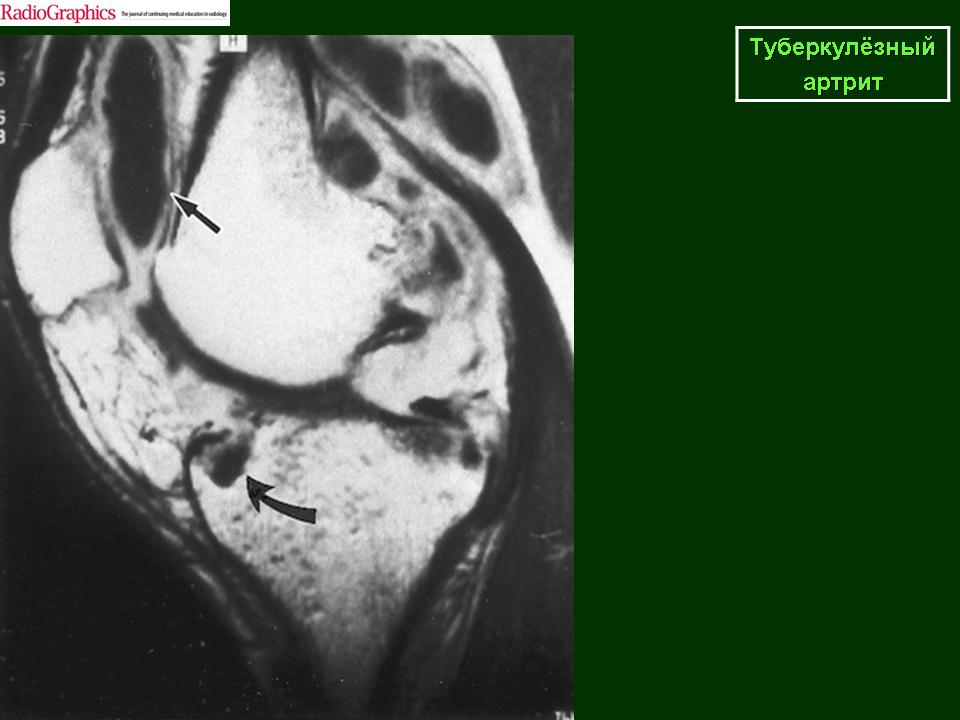

Туберкулез коленного сустава (гонит)

Поражение коленного сустава при туберкулезе встречается часто, на его долю приходится около 20% всех случаев костно-суставного туберкулеза. Общие клинические симптомы в преартритической фазе связаны с интоксикацией. Местные проявления или совсем отсутствуют, или носят неопределенный характер и мало выражены, однако больной заметно щадит пораженную конечность. Преартритическая фаза может протекать длительно, особенно в детском возрасте, в связи с тем, что эпифизы покрыты толстым суставным хрящом. Первичные очаги чаще встречаются в проксимальном эпифизе большеберцовой кости (50%) и в дистальном эпифизе бедренной кости (21,7%), реже в метафизах этих костей (соответственно в 10% и 2,3% случаев), и совсем редко в надколеннике и эпифизе малоберцовой кости (2,2%). Первым рентгенологическим симптомом туберкулезного процесса является ограниченный участок остеопороза с нечетким рисунком костных трабекул. Затем появляется нечетко очерченный очаг деструкции костной ткани, который может содержать губчатые мелкие секвестры. Очаги деструкции могут быть крупными, нередко в форме песочных часов, что характерно именно для поражения коленного сустава. При наиболее частой, эпиметафизарной локализации, очаги деструкции костной ткани обычно располагаются субкортикально. Периоститы не характерны. Артритическая фаза туберкулезного гонита характеризуется постоянством клинических проявлений. Появляется небольшая атрофия мышц, симптом Александрова, припухлость и боли в суставе, контрактуры, повышение местной температуры. Причем эти симптомы сохраняются и в покое. У некоторых детей отмечается удлинение пораженной конечности. Сустав увеличен в объеме, постепенно нарастает атрофия мышц, подвывихи голени, чаще кзади. Появляются натечные абсцессы и свищи. Рентгенологические проявления туберкулезного гонита достаточно разнообразны. Однако самым ранним симптомом перехода туберкулезного процесса на сустав является нарастающий диффузный или пятнистый остеопороз, который постепенно распространяется на кости всей конечности. Причем, чем более остро протекает туберкулезный процесс, тем более выражен остеопороз. У детей отмечается увеличение размеров эпифизов, по сравнению со здоровой конечностью, одновременно может увеличиваться ядро окостенения надколенника (симптом «постарения эпифизов» С. Л. Трегубова). Постепенно нарастает сужение суставной щели, которое иногда может быть неравномерным, больше выраженным с одной стороны. Однако этот признак иногда может быть кажущимся, и связан с небольшой сгибательной контрактурой. В таких случаях необходимо производить для сравнения рентгенографию и здорового коленного сустава в том же положении. Одновременно с сужением суставной щели появляется неровность, волнистость суставных поверхностей, затем появляется нечеткость, зазубренность, прерывистость контуров суставных поверхностей. Выявляются краевые очаги деструкции костной ткани, которые могут располагаться в противоположных отделах сочленяющихся костей и содержать секвестры, часто множественные. Секвестры кажутся более плотными, «склерозированными» на фоне выраженного остеопороза, структура их губчатая, «ноздреватая», контуры неровные. Постепенно появляются признаки истинной атрофии костей. При затихании процесса рентгенологически не отмечается прогрессирование деструкции. Контуры очагов деструкции становятся сначала четкими, а затем вокруг них появляется нежный ободок склероза. Выявляются контуры суставной щели, которая имеет причудливую форму. На уровне очагов деструкции она неравномерно расширена, а в тех отделах, где замыкательные пластинки эпифизов сохранены резко сужена. На фоне остеопороза появляются толстые, склерозированные костные балки, расположенные вдоль силовых линий. Постепенно восстанавливаются и уплотняется замыкательнные пластинки эпифизарных концов сочленяющихся костей. Суставная щель суживается, иногда вовсе не прослеживается. Костные анкилозы наблюдаются не часто, более типичны фиброзные сращения, порочное положение и подвывихи. У детей нарушается продольный рост костей и отмечается их укорочение. В менее благоприятных случаях наблюдаются обострения и рецидивы, что связано с наличием остаточных туберкулезных очагов. В этих случаях нарастают явления интоксикации и местные изменения. При рентгенологическом исследовании выявляется нарастание остеопороза, появляются очаги деструкции с нечеткими, неровными контурами, иногда содержащие секвестры. Замыкательные пластинки также теряют четкость. Деструктивные изменения могут быть значительными и приводить к дальнейшему разрушению костей, образующих сустав. Дифференциальную диагностику туберкулезного гонита приходится проводить с целым рядом заболеваний: частичным асептическим некрозом (болезнь Кенига), литическим вариантом остеобластокластомы, остеогенной остеокластической саркомой, гемофилическим артрозом и ревматоидным артритом. Болезнь Кенига встречается у взрослых. Больных беспокоят боли в коленном суставе, усиливающиеся при нагрузке. Симптомы интоксикации отсутствуют. Дифференцировать с туберкулезным процессом приходится I—II стадии болезни Кенига. Однако отсутствие остеопороза, типичная локализация краевого очага деструкции в медиальном мыщелке бедра, его небольшие размеры, относительно четкие контуры, наличие плотного с четкими контурами секвестроподобного тела, обычные размеры суставной щели — все это позволяет высказаться в пользу частичного асептического некроза. При дифференциальной диагностике с остеогенной остеокластической саркомой, которая особенно в начальных стадиях протекает без постоянных болей, может возникнуть ряд трудностей. Однако у детей остеогенная саркома локализуется в метафизе. Очаг деструкции одиночный с неровными, нечеткими контурами, не содержит секвестров, остеопороз в прилежащих отделах костной ткани не характерен. Типична периостальная реакция по смешанному типу. Раньше существовала точка зрения, что при саркоме процесс не переходит через ростковую зону. В последние годы доказана возможность у детей перехода процесса при остеогенной саркоме через ростковую зону. Однако разрушения суставного хряща и сужения суставной щели не отмечается. При литическом варианте остеобластокластомы очаг деструкции костной ткани, локализуясь в эпиметафизе у взрослых и метадиафизе у детей, чаще располагается эксцентрично, вызывая на ранних стадиях асимметричное булавовидное вздутие кости. Очаг деструкции имеет четкие контуры. Склеротическое отграничение и наличие секвестров не типично. Остеопороза в прилежащих отделах не выявляется. При проведении дифференциальной диагностики с гемофилическим артрозом необходимо учитывать клинические, анамнестические и лабораторные данные. У больных с гемартрозом отсутствуют явления интоксикации, в анамнезе имеется указание на кровоточивость, свертываемость крови замедлена. Кроме того, при гемофилии, как правило, поражаются несколько суставов. При рентгенологическом исследовании может выявляться остеопороз, который захватывает эпифизы и не бывает таким распространенным, как при туберкулезе. Может наблюдаться увеличение размеров эпифизов по сравнению со здоровой стороной. Контуры замыкательных пластинок неровные, но всегда четкие, секвестры отсутствуют. В ряде случаев может возникнуть необходимость в проведении дифференциальной диагностики с ревматоидным артритом,, который в детском возрасте иногда может начинаться с поражения одного сустава. В этих случаях необходимо учитывать длительность заболевания, клинические и лабораторные данные. При ревматоидном артрите характерна скованность движений по утрам, отсутствие симптомов интоксикации, отрицательный симптом Александрова. Туберкулиновые пробы, как правило, отрицательные. Диагностическое значение имеет положительный ревматоидный фактор в синовиальной жидкости. При рентгенологическом исследовании больных ревматоидные артритом выявляется остеопороз костей образующих коленный сустав, сужение суставной щели. У мест прикрепления капсулы сустава выявляются краевые узуры с четкими контурами и ободком склероза вокруг. При туберкулезном гоните — в эпиметафизе большеберцовой и бедренной костей выявляются очаги деструкции с нечеткими, изъеденными контурами, постепенно переходящими в остеопоротичную костную ткань. Очаги деструкции могут содержать губчатые секвестры.